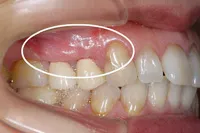

術後2ヶ月

術前に比べ、歯茎の組織が再生され、健康な状態の時とほぼ同様になりました。